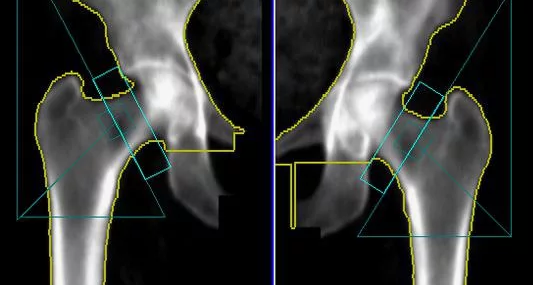

В случае перелома шейки бедра компания МосРентген Центр госпитализирует в Склиф для эндопротезирования.